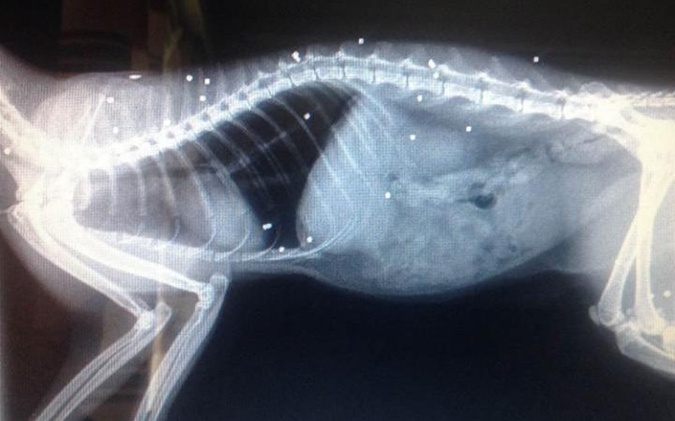

Кошка чудом выжила после 30 огнестрельных ранений

Британская кошка Кис-Кис пропала в начале апреля. Хозяева нашли ее только спустя неделю. Животное истекало кровью и едва могло ходить. Трехлетнюю Кис-Кис тут же отправили к ветеринару. Рентгеновские снимки показали, что в нее 30 (!) раз стреляли из огнестрельного оружия, пишет The Independent.

- Это чудо, что она выжила, - заявил ветеринар.

Одна из пуль попала в лапу, из-за чего Кис-Кис не может нормально ходить. Кроме того, пострадал и левый глаз кошки. Из-за пули отслоилась сетчатка, так что животное будет видеть только одним глазом.